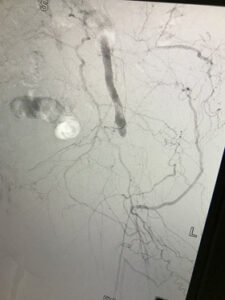

Απειλούμενη απώλεια κάτω άκρου λόγω κρίσιμης ισχαιμίας – επιτυχή διάσωση

Ενδαγγειακή αποκατάσταση απόφραξης της επιπολής μηριαίας αρτηρίας

ελάχιστα παρεμβατική μέθοδος

24 ωρη παραμονή